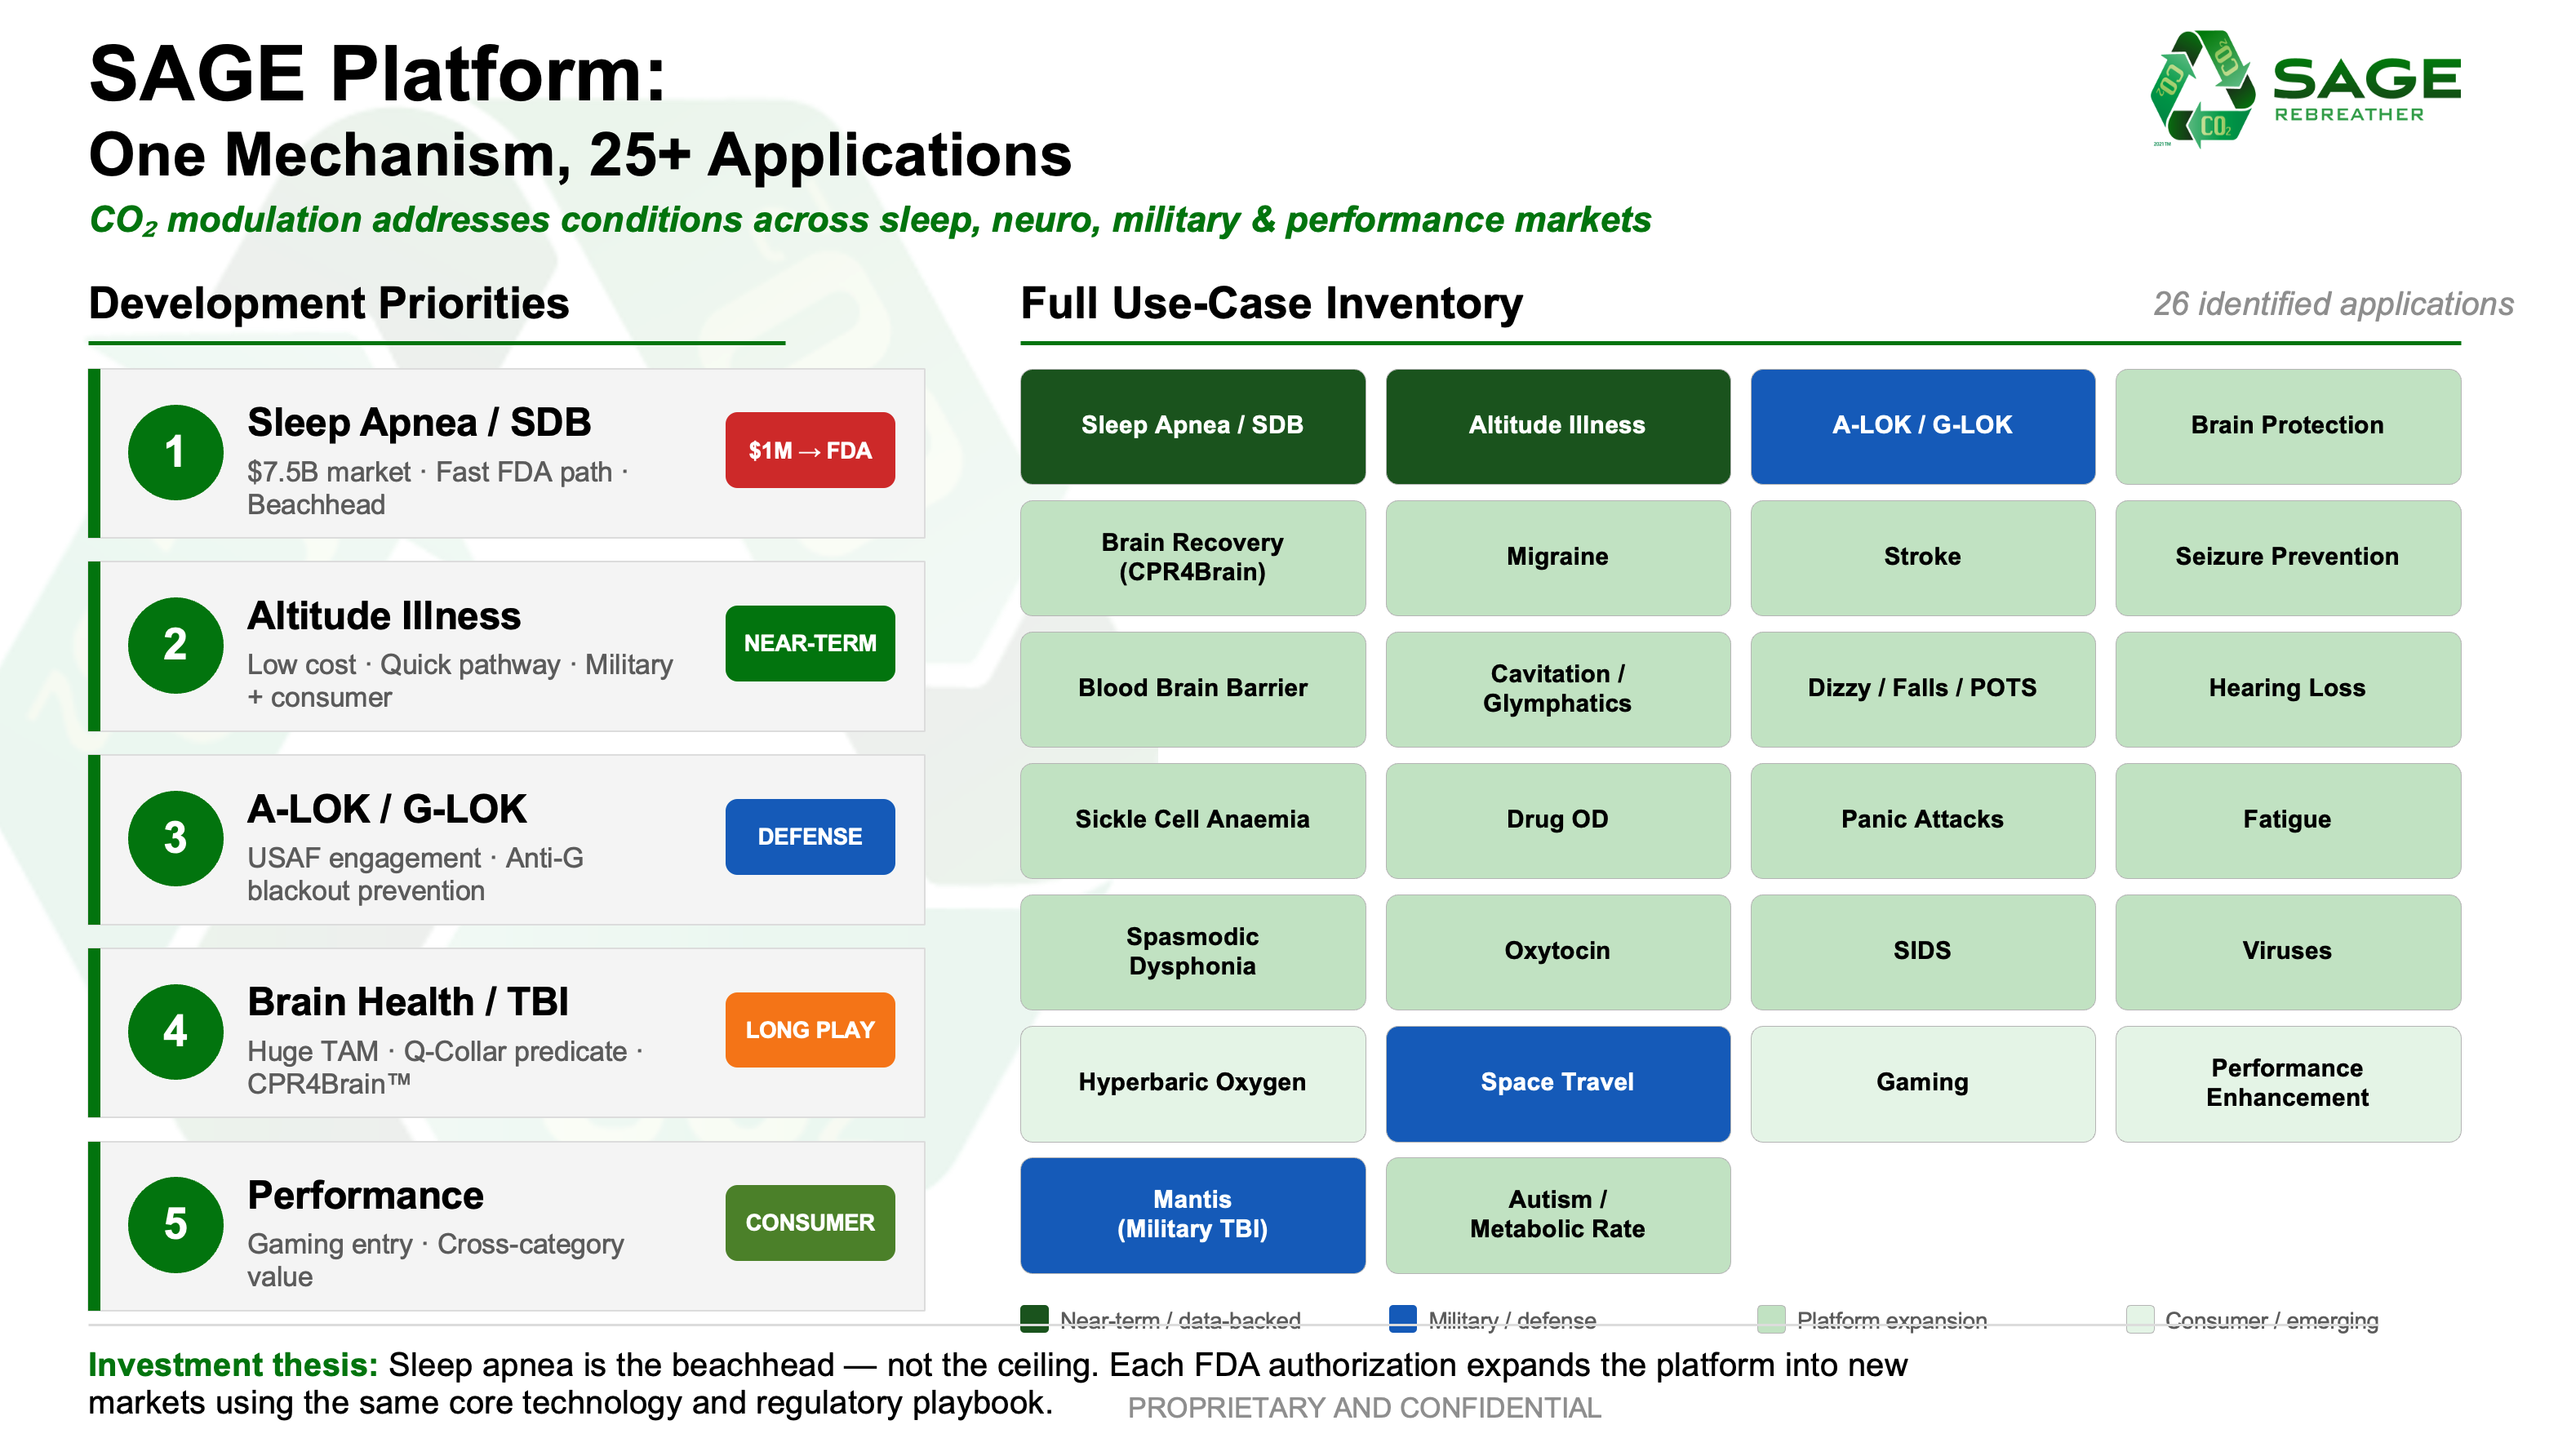

… dramatically improving a broad spectrum of debilitating human conditions including…

Sleep Apnea

Altitude Illness, and

Reversing Brain Injury

Our SAGE Rebreather opens the door for making life better for millions. Our platform technology appears to be able to overcome 15+ adverse human conditions measuring in excess of 2 billion people worldwide. Here are the numbers we've been able to find for just the first three use-cases...

Here’s the full list (so far) of human conditions we believe* will be relieved by effectively modulating (like a snorkel) one’s CO2 level through our innovative SAGE Rebreather™...